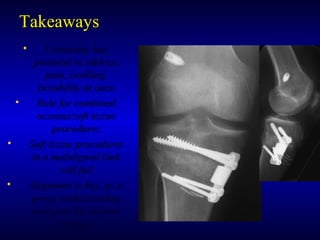

TakeawaysTakeaways

• Osteotomy hasOsteotomy has

potential to addresspotential to address

pain, swelling,pain, swelling,

instability at onceinstability at once

• Role for combinedRole for combined

osseous/soft tissueosseous/soft tissue

proceduresprocedures

• Soft tissue proceduresSoft tissue procedures

in a malaligned limbin a malaligned limb

will failwill fail

• Alignment is key, as isAlignment is key, as is

preop understandingpreop understanding

and plan for desiredand plan for desired

changeschanges